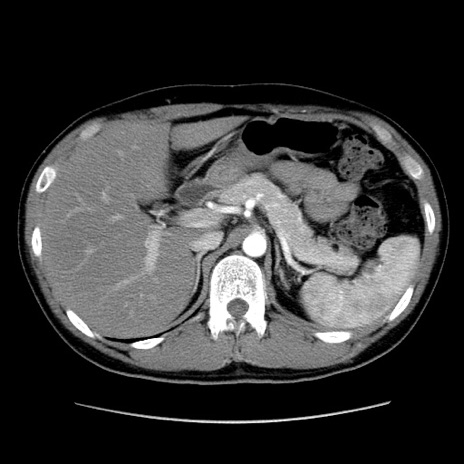

冠状断像

【症例】20歳代 男性

【主訴】心窩部痛

【現病歴】今朝より上腹部痛あり。一旦軽快していたが再度出現したため救急要請。昨日夕に白身の魚を含む刺身を食べた。

【身体所見】BP 136/89mmHg、HR 74/min、BT 37.0℃、腹部:膨満、軟、心窩部に圧痛あり。反跳痛なし、筋性防御なし、腸雑音やや亢進あり。

【データ】WBC 17700、CRP 0.48